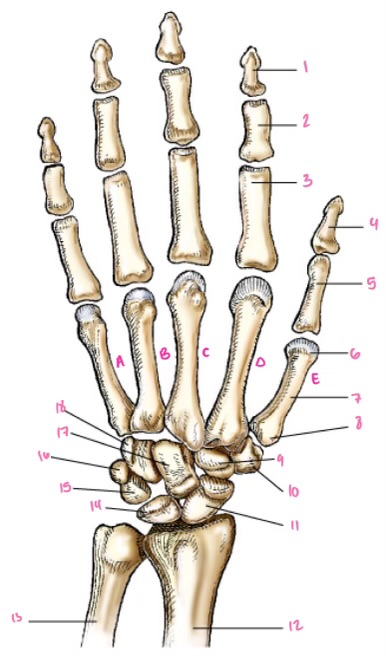

1

1

2

2

3

3

4

9

5

10

6

11

7

14

8

15

9

16

10

17

11

18

12

1

13

2

14

3

15

4

16

5

17

6

18

7

19

8

20

9

7

22

8

23

9

24

10

25

11

26

13

14

15

16

17